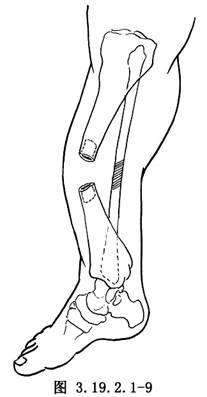

遊離骨端,切除遠、近端硬化的骨組織(圖3.19.2.1-7)。鑽通和擴大遠近端髓腔(圖3.19.2.1-8)。手法矯正脛骨向前成角畸形,並使健康的脛骨遠、近端互相嵌壓。有時需另做切口延長跟腱,以利脛骨成角畸形矯正。如腓骨完整使脛骨兩斷端分離,應另做切口,切除一段腓骨,才能使脛骨兩斷端對正(圖3.19.2.1-9)。以斯氏釘逆行法髓內固定切斷的腓骨(圖3.19.2.1-10)。這樣對脛骨的斷端也提供了良好的對位和固定作用。在手法矯正向前成角畸形時,最好使脛骨矯正到向後成角15°~20°(圖3.19.2.1-11)。